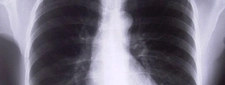

Temiz akciğer tomografisi, akciğerlerde anormal bulguların olmadığını gösteren önemli bir görüntüleme sonucudur. Bu sonuç, akciğer sağlığının iyi olduğunu ve olası hastalıkların tespit edilmediğini belirtir. Ancak, kesin tanı için sağlık profesyoneli ile görüşmek gereklidir.

Temiz Akciğer Tomografisi Ne Anlama Geliyor?Günümüzde tıpta tanı ve tedavi süreçlerinde önemli bir yer tutan görüntüleme yöntemlerinden biri olan akciğer tomografisi, hastalıkların teşhisinde kritik bir rol oynamaktadır. "Temiz akciğer tomografisi" ifadesi, genellikle akciğerlerde herhangi bir anormal bulguya rastlanmadığı anlamına gelir. Bu bağlamda, temiz bir akciğer tomografisi sonucu, hastanın akciğer sağlığının iyi olduğunu gösterir. Akciğer Tomografisi Nedir?Akciğer tomografisi, yüksek çözünürlüklü görüntüler elde etmek için X-ray teknolojisini kullanan bir görüntüleme yöntemidir. Bu yöntem, akciğerlerin iç yapısının detaylı bir şekilde incelenmesine olanak tanır. Tomografi, akciğerlerdeki lezyonlar, tümörler, enfeksiyonlar ve diğer patolojilerin tespit edilmesinde son derece etkili bir yöntemdir. Temiz Akciğer Tomografisi SonucuTemiz bir akciğer tomografisi sonucu, şu durumları ifade edebilir:

Bu sonuç, genellikle hastanın akciğer sağlığının iyi olduğunu ve herhangi bir ciddi patoloji olmadığını gösterir. Ancak, bu sonuçlar her zaman kesin bir tanı anlamına gelmez; doktorun klinik değerlendirmesi ve hastanın genel sağlık durumu da göz önünde bulundurulmalıdır. Temiz Akciğer Tomografisinin ÖnemiTemiz akciğer tomografisi sonucu, özellikle kronik akciğer hastalığı, kanser riski veya enfeksiyon öyküsü bulunan hastalar için büyük bir rahatlık kaynağıdır. Bu durum, hastaların tedavi süreçlerine olumlu yönde katkı sağlar ve gereksiz endişeleri azaltır. Ayrıca, temiz bir tomografi sonucu, sağlık profesyonellerine hastanın durumu hakkında daha fazla bilgi verir ve gelecekteki muayene ve tedavi planlamalarına yardımcı olur. SonuçTemiz akciğer tomografisi, akciğer sağlığının iyi olduğunu gösteren önemli bir bulgudur. Ancak, bu sonucun değerlendirilmesi için mutlaka bir sağlık profesyoneliyle görüşülmesi gerektiği unutulmamalıdır. Her durumda, kişinin genel sağlık durumu, belirtiler ve diğer tetkiklerin sonuçları birlikte ele alınmalıdır. Sağlıklı bir yaşam tarzı, düzenli kontroller ve zamanında yapılan tetkikler, akciğer sağlığının korunmasında önemli rol oynamaktadır. |